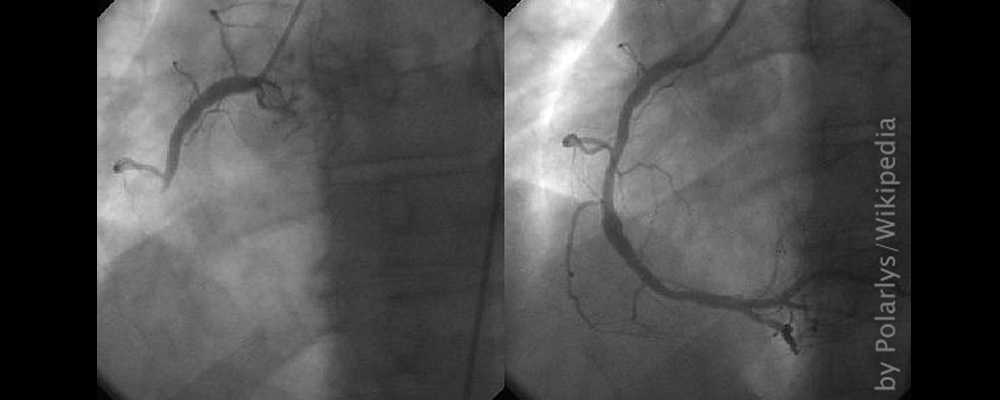

Vor dem Rückflug nach Deutschland wird jedoch zunächst eine Koronarangiographie1 veranlasst. Mit Hilfe dieser Untersuchung können Engstellen gefunden und ggf. sofort revidiert werden. Gleich nach dem Verfahren ist klar: Eine OP mit einem sogenannten Stent, einer inneren Gefäßstütze, ist dringend erforderlich. Ansonsten ist der Rückflug wegen des geringen Kabinendrucks im Flugzeug nicht zu verantworten. Die Operation könnte sogar direkt im Krankenhaus vor Ort durchgeführt werden. In der Zwischenzeit werden alle Medical Reports vom Krankenhaus an aqua med weitergeleitet und von den aqua med Ärzten mit beurteilt – die Zusammenarbeit klappt hervorragend und reibungslos.

Die Operation erfolgt bei vollem Bewusstsein. „Geplant war es, dass sie mir einen Stent einsetzen und ich nach einer halben Stunde mit der OP durch bin“, erinnert sich Stefan. Aber noch während der Operation wird Stefan mitgeteilt, dass 4 weitere Stents gesetzt werden müssen. „Ich konnte die gesamte Operation auf Monitoren verfolgen. An Stellen meiner Arterien im Herzen konnte ich sehen, dass diese in sich zusammen gefallen waren, ganz schön beunruhigend“, so Stefan. Doch nun sitzen dort die Stents.

1 bildgebendes Verfahren zur Darstellung der Herzkranzgefäße mittels Kontrastmittelgabe über einen Herzkatheter